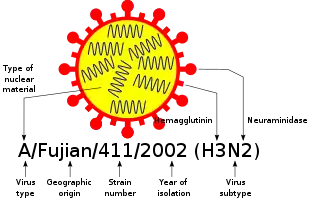

IAV is responsible for most cases of severe illness as well as seasonal epidemics and occasional pandemics. It infects people of all ages but tends to disproportionately cause severe illness in the elderly, the very young, and those who have chronic health issues. Birds are the primary reservoir of IAV, especially aquatic birds such as ducks, geese, shorebirds, and gulls,[15][16] but the virus also circulates among mammals, including pigs, horses, and marine mammals. IAV is classified into subtypes based on the viral proteins haemagglutinin (H) and neuraminidase (N).[17] As of 2019, 18 H subtypes and 11 N subtypes have been identified. Most potential combinations have been reported in birds, but H17-18 and N10-11 have only been found in bats. Only H subtypes H1-3 and N subtypes N1-2 are known to have circulated in humans,[17] the current IAV subtypes in circulation being H1N1 and H3N2.[2] IAVs can be classified more specifically to also include natural host species, geographical origin, year of isolation, and strain number, such as H1N1/A/duck/Alberta/35/76.[1][9]